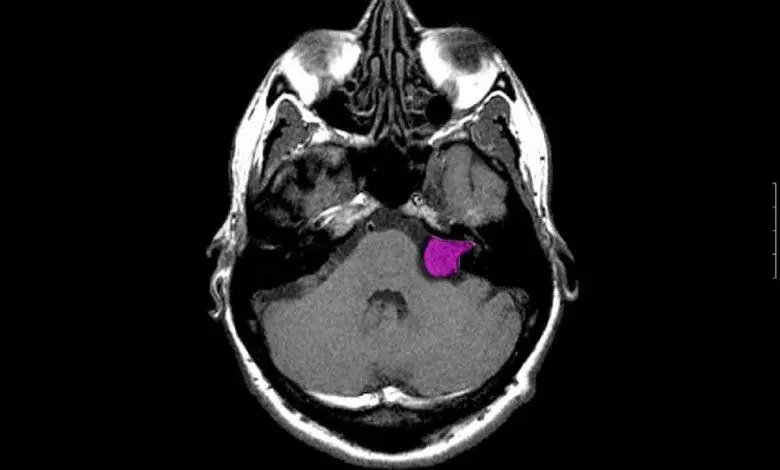

- Imagerie par résonance magnétique (IRM) : L’IRM est l’outil de choix pour confirmer la présence du neurinome acoustique. Elle permet de localiser la tumeur, d’en déterminer la taille et de voir si elle a envahi les structures adjacentes.

- Tomodensitométrie (TDM) : Utilisée dans certains cas, notamment lorsque l’IRM n’est pas possible, la TDM permet également de détecter des tumeurs dans l’oreille interne.

Lorsque le neurinome est de petite taille et ne provoque pas de symptômes significatifs, une approche de surveillance active peut être recommandée. Cela consiste à surveiller la tumeur avec des IRM régulières pour détecter toute croissance éventuelle.

Dans l’un ou l’autre des traitements cités, un contrôle par IRM sera fait tous les 6 mois au début, puis tous les ans, puis tous les 5 ans, afin de bien surveiller l’évolution et détecter éventuellement une récidive.

Le diagnostic de neurinome de l’acoustique repose principalement sur des examens audiométriques et l’imagerie par résonance magnétique (IRM). L’audiométrie permet de détecter une perte auditive unilatérale, tandis que l’IRM identifie la tumeur sur le nerf acoustique et évalue sa taille et son emplacement. D’autres tests, comme les potentiels évoqués auditifs, peuvent également être réalisés pour compléter le diagnostic.